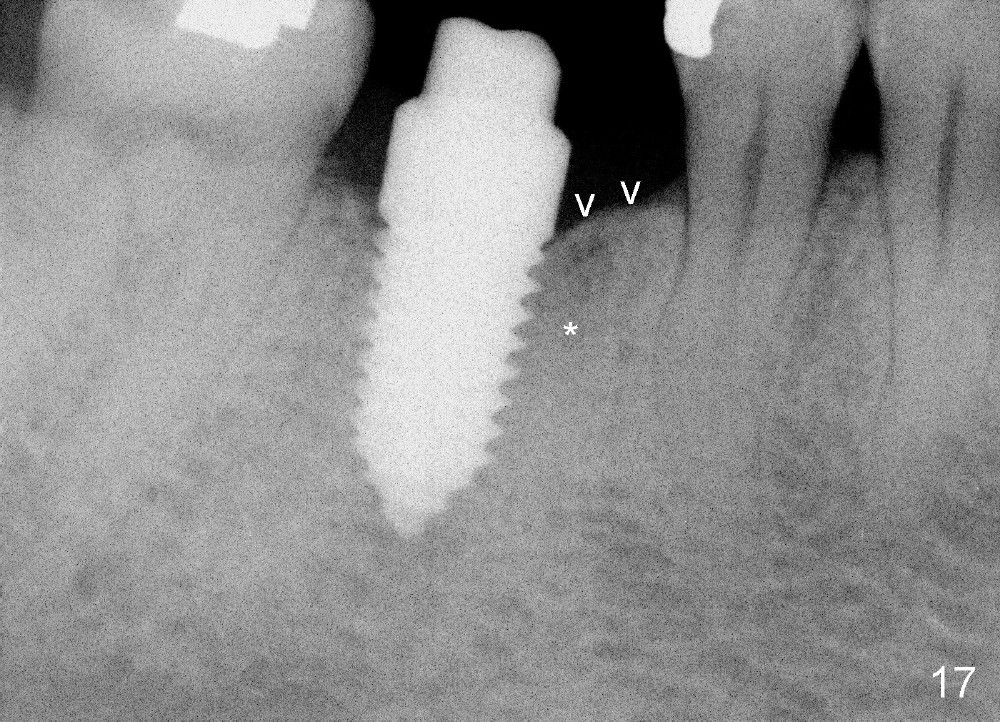

A 38-year-old lady agrees to have implant placement 7 years after loss of the crown of the lower right first molar (Fig.1,2). When the tooth is extracted, the septum is found to be low (Fig.3,4). To confirm it, a PA is taken (Fig.5). To initiate an osteotomy in the septum, it is trans-sectioned with thin osteotomes as shown in Fig.4 insert (black line). A 2 mm pilot drill is placed in the septum (Fig.6: P). The osteotomy is enlarged by 2.5-4.0 mm reamers (Fig.7,8), followed by insertion of 6x17 mm tapered tap at the depth 14 mm (Fig.9). The osteotomy is further enlarged by 4.5 and 5.0 mm reamers. A 6.0x14 mm one piece implant is placed initially. The trajectory is not ideal. A 6.0x14 mm one piece implant is placed initially. The trajectory is not ideal. The implant is removed from the osteotomy partially and reinserted with improved trajectory (Fig.11, compare to Fig.10 (red line)). Primary stability is high. There is not much bone mesiodistally so that the trajectory is easily changed in that direction. After abutment preparation, mixture of autogenous bone (harvested from reamers) and allograft is placed in the residual mesial and distal sockets (Fig.12). To contain the bone graft, an immediate provisional is placed (Fig.13 P). The occlusal plane of the provisional is significantly lower than that of the adjacent teeth to avoid micromovement of the implant. The patient is advised to eat soft food on the left side. Six days postop, the patient returns for prophy. The provisional is removed; the bone graft appears to be incorporating into the socket (Fig.14). After recementation, the provisional remains in place for 3.5 months; PA shows increased bone density in the mesial and distal sockets (Fig.15, compare to Fig.5,11). Due to insurance coverage, the patient defers fabrication of definitive restoration for at least 7 months. The immediate provisional is finally lost 8.5 months postop: the gingiva attaches to the 1-piece implant (Fig.16), while the density of the mesial socket increases (Fig.17 *) with formation of the cortex (lamina dura) coronally (v). Before the provisional (Fig.18 P) is removed for cementation of the definitive restoration, black shadow (*) is noted over the buccal gingiva. It is partially due to buccal placement (Fig.19) and partially due to buccal atrophy over a period of 10.5 months postop. How to prevent buccal placement? Positioning the first pilot drill in the septum buccolingually is a key. Eleven months post crown (Fig.20 C) cementation, the black shadow remains, but there is no tenderness. If the implant threads are immediately underneath the periosteum, there is tenderness.

CBCT taken 15 months post cementation shows that the implant is buccally placed (Fig.21 B), associated with possible postop buccal plate resorption (as compared to Fig.23 (coronal section of the site of #19). The buccal plate is not only thinner than the lingual one, but also concave (Fig.22 <). The tooth center (i.e., septum; Fig.23 T) is more buccally located than the center of the basal bone (B). Considering the denser bone lingually, the initial osteotomy should be more lingually (^). If the implant develops infection, it will be replaced by a more lingually placed implant (Fig.24 green).